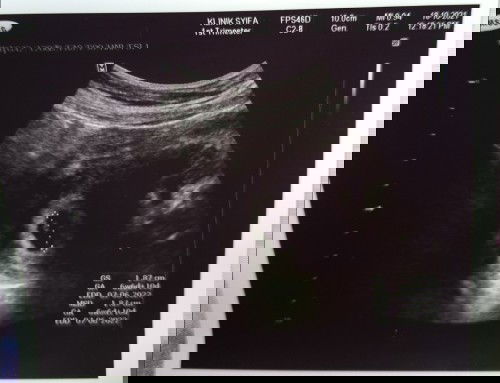

Kiraan sy 6w5d tapi 1st scan showing 6w6d.. sy scan awal sbb cramping yg kuat mlm smlm.. thank god ad keluar pd screen scan.. walau tiada bleeding, rasa perubahan mual.. god willing, sy akan update lg.. doakan sy #1stbaby